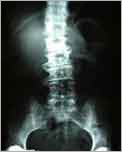

Röntgen Mit dem Röntgenbild beginnt die Abklärung von Wirbelsäulenbescherden.